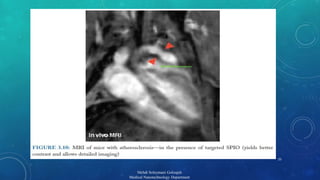

MAGNETIC NANOPARTICLES

 Super-paramagnetic Iron Oxide(SPIO)

Applications:

 Passive Targeting

 Active Targeting

 Cell Tracking

 Magnetic Relaxation Switching(MRS)